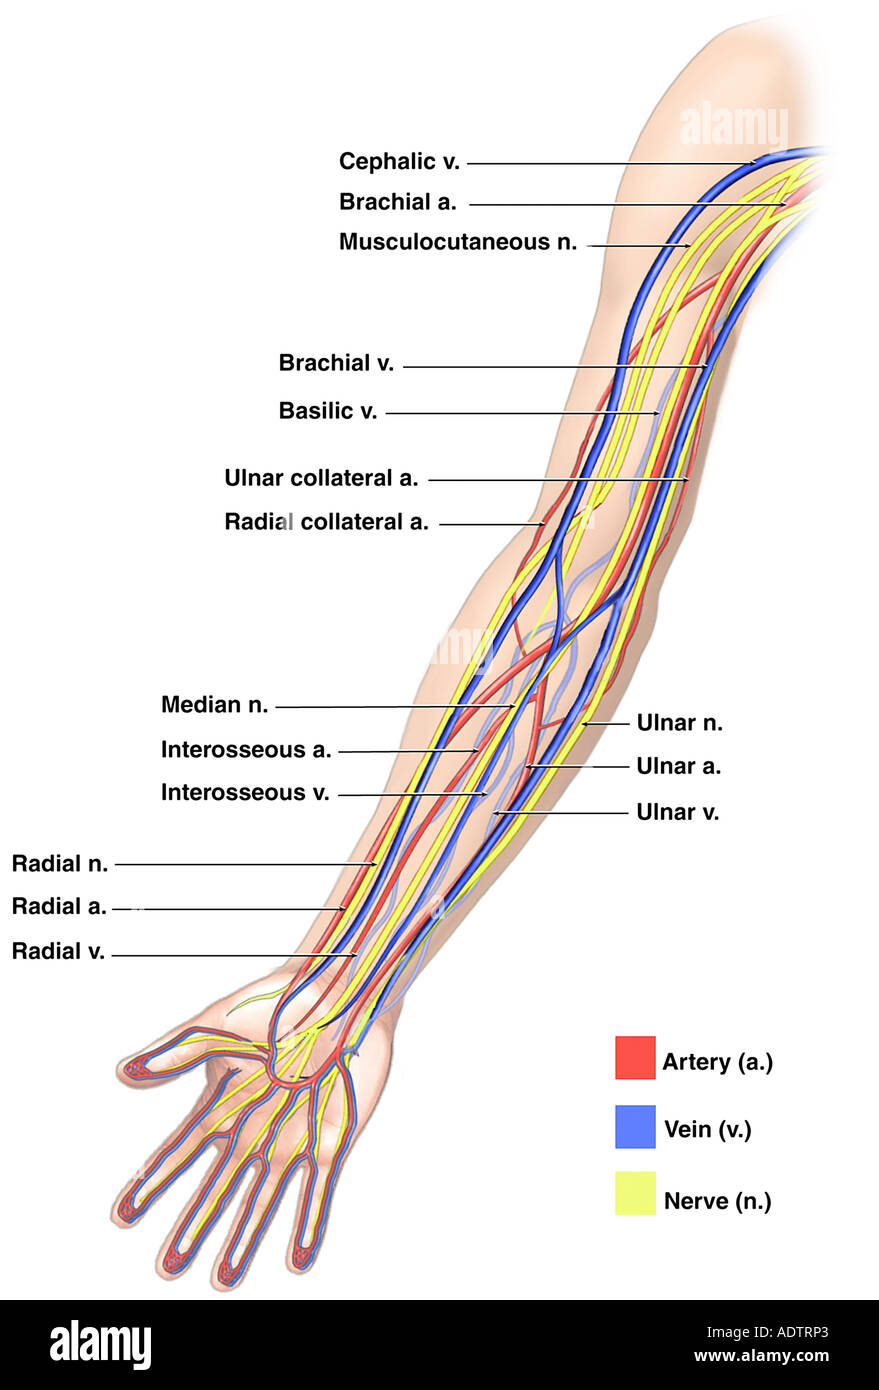

arm veins vein anatomy cephalic upper brachial human basilic nerve blood exits oxygenated musculoskeletal heart medicinebtg visit other picture

Veins Arm Hi-res Stock Photography And Images - Alamy

veins arm illustration vector alamy stock major high

arm anatomy veins vein forearm human upper shunt basilic greys hand reference radial limb side venous median anatomical runs cephalic

arm veins arteries upper anatomy limb nerves extremity stock picture alamy blood medicinebtg